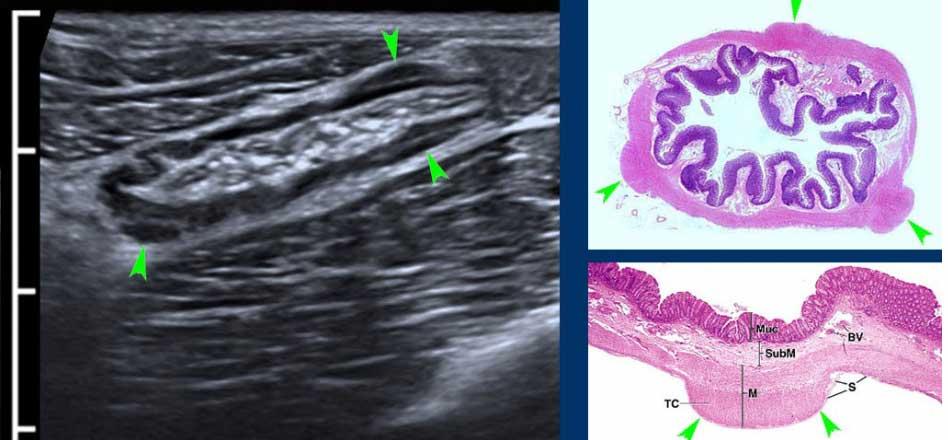

Normal small bowel in the longitudinal plane.

Jejunum

Hỗng tràng (hình bên trái) chủ yếu nằm ở góc phần tư trên trái, và chứa nhiều nếp van Kerckring (van hồi manh tràng) hơn so với hồi tràng (hình bên phải), vốn nằm nhiều hơn ở góc phần tư dưới phải.